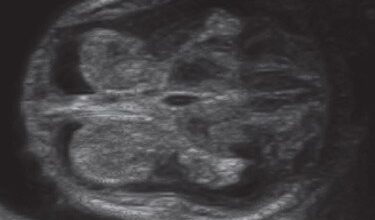

La evolución del feto a través de ecografías

Ecografía con 25 semanas: en esta ecografía, se visualiza las diferentes estructuras del cerebro, y también se analizan las arterias cerebrales (coloreadas).